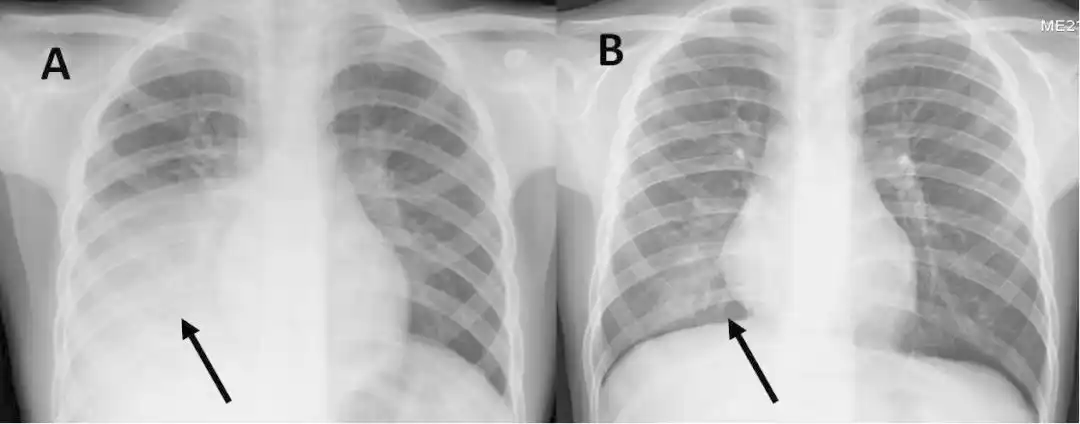

【讨论】两例患儿的胸片

这几组患儿胸片是肺炎还是正常影像规培医师懵了